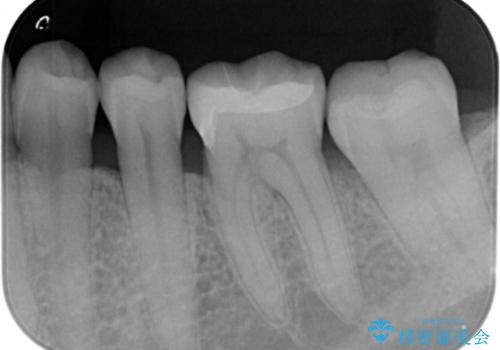

- 銀の詰め物が目立つので白くしたいとのことで来院。

拡大鏡下で銀の詰め物を除去して虫歯がない事を確認して

白い詰め物(e-maxインレー)にてやりかえを行いました。

e-maxインレーはセラミックの詰め物の事です。

セラミックは銀の詰め物に比べて虫歯になりにくい性質があります。

白い詰め物が入り、大変満足して頂けました。